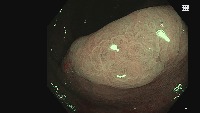

Disease Diagnosis: The "Manifold learning" model can be applied in the medical field to facilitate early detection and diagnosis of oral diseases. By identifying and distinguishing between Adenoma, Hyperplasic, and Adenocarcinoma, this model can assist doctors in understanding a patient's condition and deciding the appropriate treatment method.

Medical Education: The model can be used as a learning tool in medical schools and universities for studying oral diseases. It can aid students in understanding and distinguishing the different classes of oral conditions, providing them with practical insights that textbooks might not offer.

Dental Consultation: Dentists can incorporate this model into their practice to identify and prevent potential oral diseases at a very early stage. This can improve the patient's oral health and could even prevent life-threatening situations with early detection of Adenocarcinoma.

Pharmaceutical Research: Pharmaceutical companies can use this model to analyze the effects of their drugs under development. By observing changes in the mouth before and after treatment, they can track the drug's efficacy in treating these oral conditions.

Telemedicine Applications: The model could be used in telehealth applications to enable remote oral health assessments. This can facilitate patients to get diagnostic reports from the comfort of their homes without physical visits to the hospital or clinic.